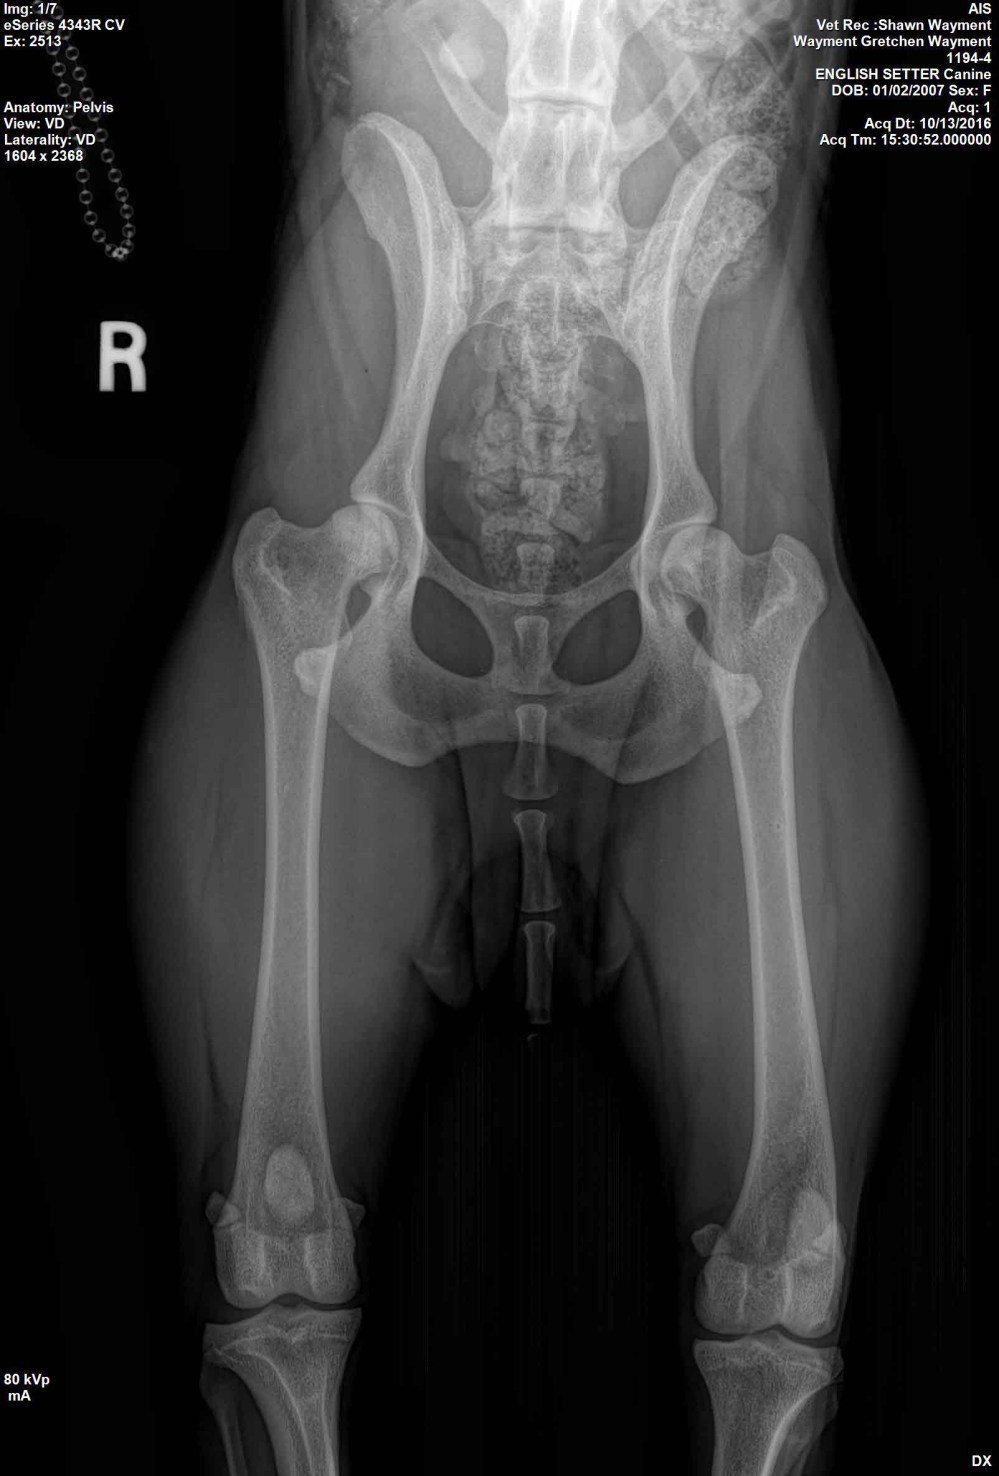

Ron Boehme, the host of the awesome Hunting Dog Podcast, asked if I ‘d contribute some veterinary specific advice to his Blog on the Hunting Dog Podcast…which I gladly accepted the challenge. Here’s the link to my latest contribution http://thehuntingdogpodcast.com/2017/04/canine-hip-dysplasia-and-pennhip/.